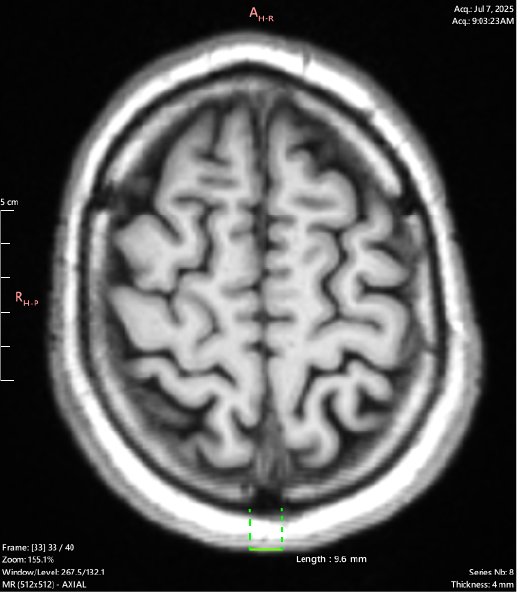

T1 Axial

Again showing a 12.4mm outside margin for the Sagittal suture. This slice shows both cranial sutures (Sagittal + Coronal) are displaying the same hypointense tissue signal along the entirety of their visible length.

It also demonstrates that this osteolytic process is not confined to the sutures along, and has spread to the surrounding bone including the cortical layer (black rim around the white signaling marrow).

The fibrous tissue entity is also shown as invading the subcutaneous fat layer (white around the cortical bone), and the skin.

< - (Length 9.6mm)